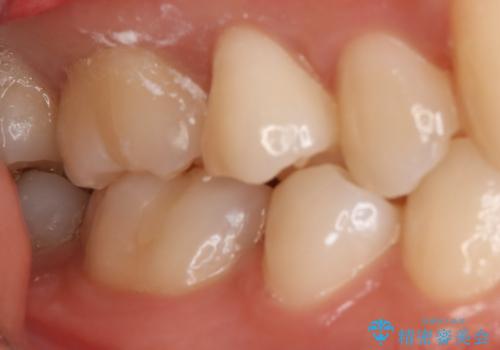

- 右上6番の保険材料で詰められた部分をセラミックにやり変え希望の患者様です。

切削量などを考慮し、セラミックインレーでの治療を選択しました。

う蝕が深くまで進行していたので、全て除去した上でCR裏層を行い形成、印象を行っています。